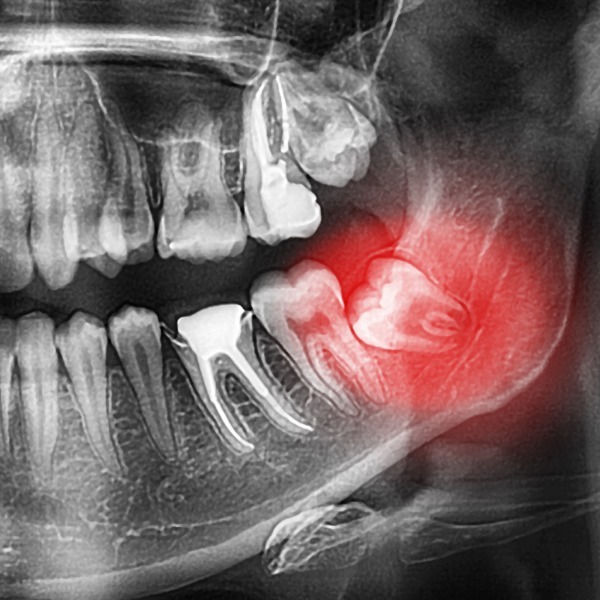

Wisdom Tooth Infection Pacific Oral Surgery Pacific Oral Surgery Oral Surgery Complications Management Stresses recognition of the medically compromised patient is paramount in order to deliver successful treatment. Consider an elective surgical approach, if within your competency, if the patient is deemed at high risk of fracture. Early recognition and prompt management of complications and emergencies distinguishes the experienced surgical practitioner from the novice. Having a prepared oral surgery complication kit may save. Oral Surgery Complications Management.